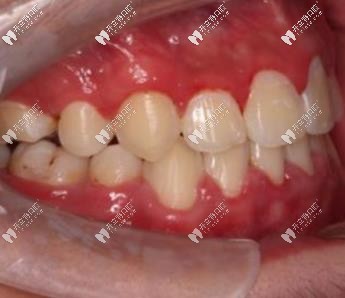

可以看到,本來(lái)?yè)頂D的牙齒已經(jīng)排列整齊,咬合也已經(jīng)調(diào)整對(duì)稱,誰(shuí)說(shuō)地包天不能矯正呢!這個(gè)效果是不是很贊呢!

在此想給更多小伙伴提醒一句的是:骨性地包天分為一度、二度、三度,輕度是可以通過(guò)牙套進(jìn)行矯正過(guò)來(lái)的,而重度的只能做正頜+正畸聯(lián)合治療啦!建議經(jīng)過(guò)專業(yè)設(shè)備檢查后確定牙齒情況!